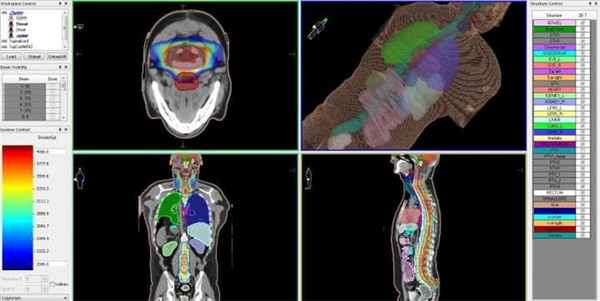

Линейный ускоритель Elekta

Если объем новообразования достаточно большой, и не позволяет применить радиохирургический метод, лечение эпендимомы предусматривает удаление злокачественного очага хирургическим путем с последующим облучением на высокоточном линейным ускорителе с функцией IMRT.

Лучевое лечение эпендимомы головного мозга на линейном ускорителе с принципом IMRT во многом соответствует принципу радиохирургического лечения опухолей на КиберНоже. Точность лучевой терапии, также как и при радиохирургии, обеспечивает контролируемая доставка высокой дозы ионизирующего излучения точно в объем опухоли, пространственные контуры которой составлены компьютерной системой планирования.

Перед тем как приступить к лечению, пациент проходит комплексную КТ- и МРТ-диагностику, на основании результатов которой лучевым терапевтом совместно с медицинским физиком составляется цифровая компьютерная трехмерная модель расположения опухоли и здоровых тканей вокруг нее, которые не должны быть подвергнуты облучению.

Эпендимома головного мозга — план лечения на линейном ускорителе, с распределением доз облучения для различных типов биологических тканей

Принцип действия IMRT-лучевой терапии состоит в том, что для каждой зоны, в соответствии с виртуальной компьютерной моделью, задаются максимальные и минимальные дозы ионизирующего облучения. Это позволяет доставлять в границы опухоли и пути ее метастазирования максимально высокие дозы излучения, необходимые для разрушения раковых клеток, а в зону расположения критических структур головного мозга — нулевые.

После того, как план лечения утвержден, пациенту назначается первый сеанс (фракция) лучевой терапии. Лечение проходит амбулаторно и не требует анестезии. Во время сеанса лучевой терапии пациент удобно располагается на специальном столе, а подвижная часть линейного ускорителя последовательно занимает различные положения, подавая необходимую дозу ионизирующего излучения в опухолевый очаг. Конфигурация каждого пучка излучения, точно повторяющего форму опухоли, формируется многолепестковым коллиматором, который управляется системой согласно заданному плану и контролируется ответственным врачом.

Лучевая терапия IMRT проводится таким образом, что наиболее высокие дозы облучения, необходимые для гибели раковых клеток, доставляются только в границы опухоли, а здоровые ткани вокруг нее поддаются наименьшему влиянию облучения. При этом наиболее важные структуры организма (ствол мозга, аорта, слюнные железы и др.) во время лучевой терапии абсолютно защищены — для них еще на стадии планирования лечения задается зона нулевого воздействия, так называемая «холодная зона».

Лечение на линейном ускорителе, как правило, не требует никакой специальной подготовки пациента – во время фракций лучевой терапии пациент находится в сознании, а подвижная часть линейного ускорителя последовательно занимает указанные в плане лечения положения, в каждом из которых проводится излучение требуемого поля. Количество фракций зависит от множества индивидуальных факторов, поэтому длительность, состав терапии и стоимость лечения определяются для каждого пациента его лечащим врачом. После завершения каждого сеанса лучевого лечения, каждый из которых длится в среднем 30-40 минут, пациент может вернуться к обычному распорядку своего дня